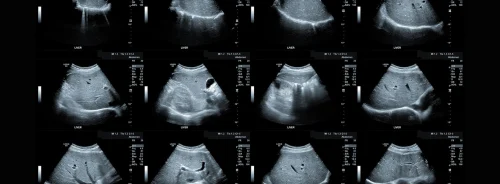

The TULSA procedure involves inserting a small catheter-like device through the urethra into the prostate gland. Utilizing MRI technology, precise positioning of therapeutic ultrasound elements is guided into the prostate, allowing for targeted treatment of cancerous tissues. MR thermometry is employed to monitor tissue temperatures, ensuring that the prostate tissue is heated to more than 55 degrees Celsius while protecting sensitive surrounding nerves. This precision targeting and monitoring enable the destruction of cancer cells while minimising damage to healthy tissues, achieving what Dr Raman refers to as the "ultimate trifecta" in prostate cancer treatment: full local cancer control, preservation of urinary continence, and maintenance of erectile function. One of the notable advantages of the TULSA procedure is its flexibility in treatment settings. The procedure can be performed in either outpatient or in-patient facilities under general or spinal anaesthesia, typically taking two to three hours to complete. This versatility allows for personalised treatment plans tailored to individual patient needs and preferences, enhancing overall treatment outcomes and patient satisfaction.